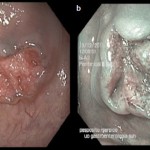

La cromomagnificazione endoscopica virtuale

La cromomagnificazione endoscopica virtuale: una tecnica innovativa e non invasiva nella diagnosi precoce del carcinoma orale. Studio preliminare su 31 casi

Autore: Dott.ssa Enrica Gentile

Relatore: Ch.mo...